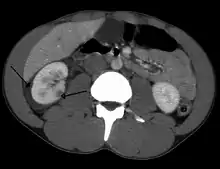

Spleen

Spleen is the most common cause of massive bleeding in blunt abdominal trauma to a solid organ. Spleen is the most commonly injured organ. A laceration of the spleen may be associated with hematoma.[13] Because of the spleen's ability to bleed profusely, a ruptured spleen can be life-threatening, resulting in shock. However, unlike the liver, penetrating trauma to the spleen, pancreas and kidneys do not present as much of an immediate threat of shock unless they lacerate a major blood vessel supplying the organs, such as the renal artery.[5] Fractures of the left lower ribs are associated with spleen lacerations in 20 percent of cases.[9]